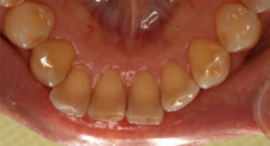

PMTC・歯のクリーニング前